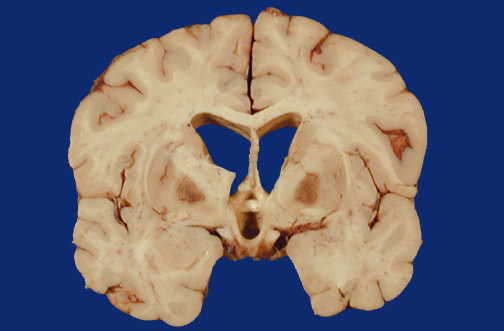

| The globus pallidus bilaterally exhibits evidence for toxic injury with a red discoloration from hyperemia, edema, and necrosis as a consequence of carbon monoxide poisoning. The poisoning may be chronic, with neurologic symptoms appearing somewhat acutely. |